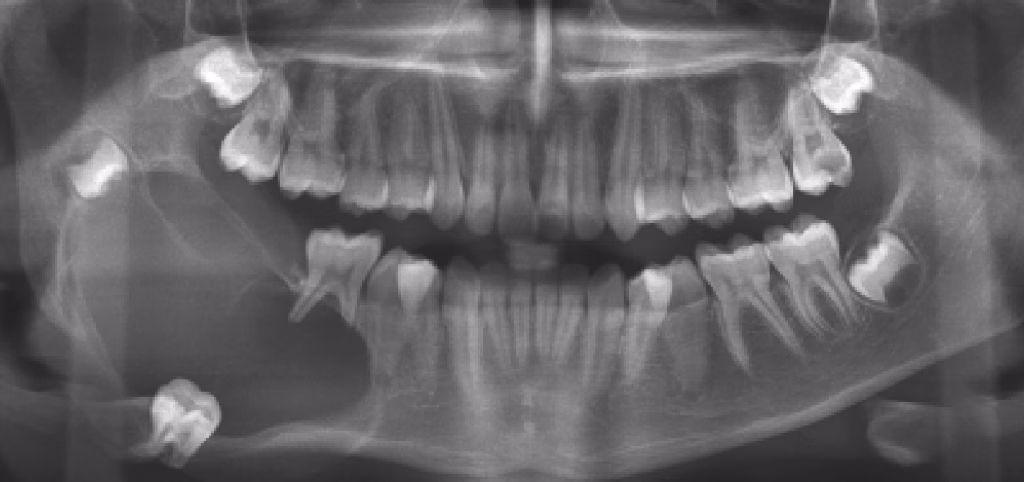

While the word “tumor” can sound frightening, benign odontogenic tumors are slow-growing, treatable, and rarely life-threatening. Dentists usually find them early during routine X-rays.

- A finding on an X-ray with no symptoms at all

- A cyst-like area on X-rays

- Looks like a simple cyst on X-ray

- Shows small “white spots” inside the lesion on X-rays

- Often found around an unerupted canine

- Looks like a simple cyst on X-rays

- Looks like tiny miniature teeth on the X-ray

- Appears as a solid, mixed-up mass of tooth material

A “honeycomb” or “tennis racket” pattern on X-ray.

- A round, well-defined area on X-ray

- A bright, round mass fused to the tooth root on X-ray

- Shows a well-defined border with mixed radiolucent/radiopaque areas